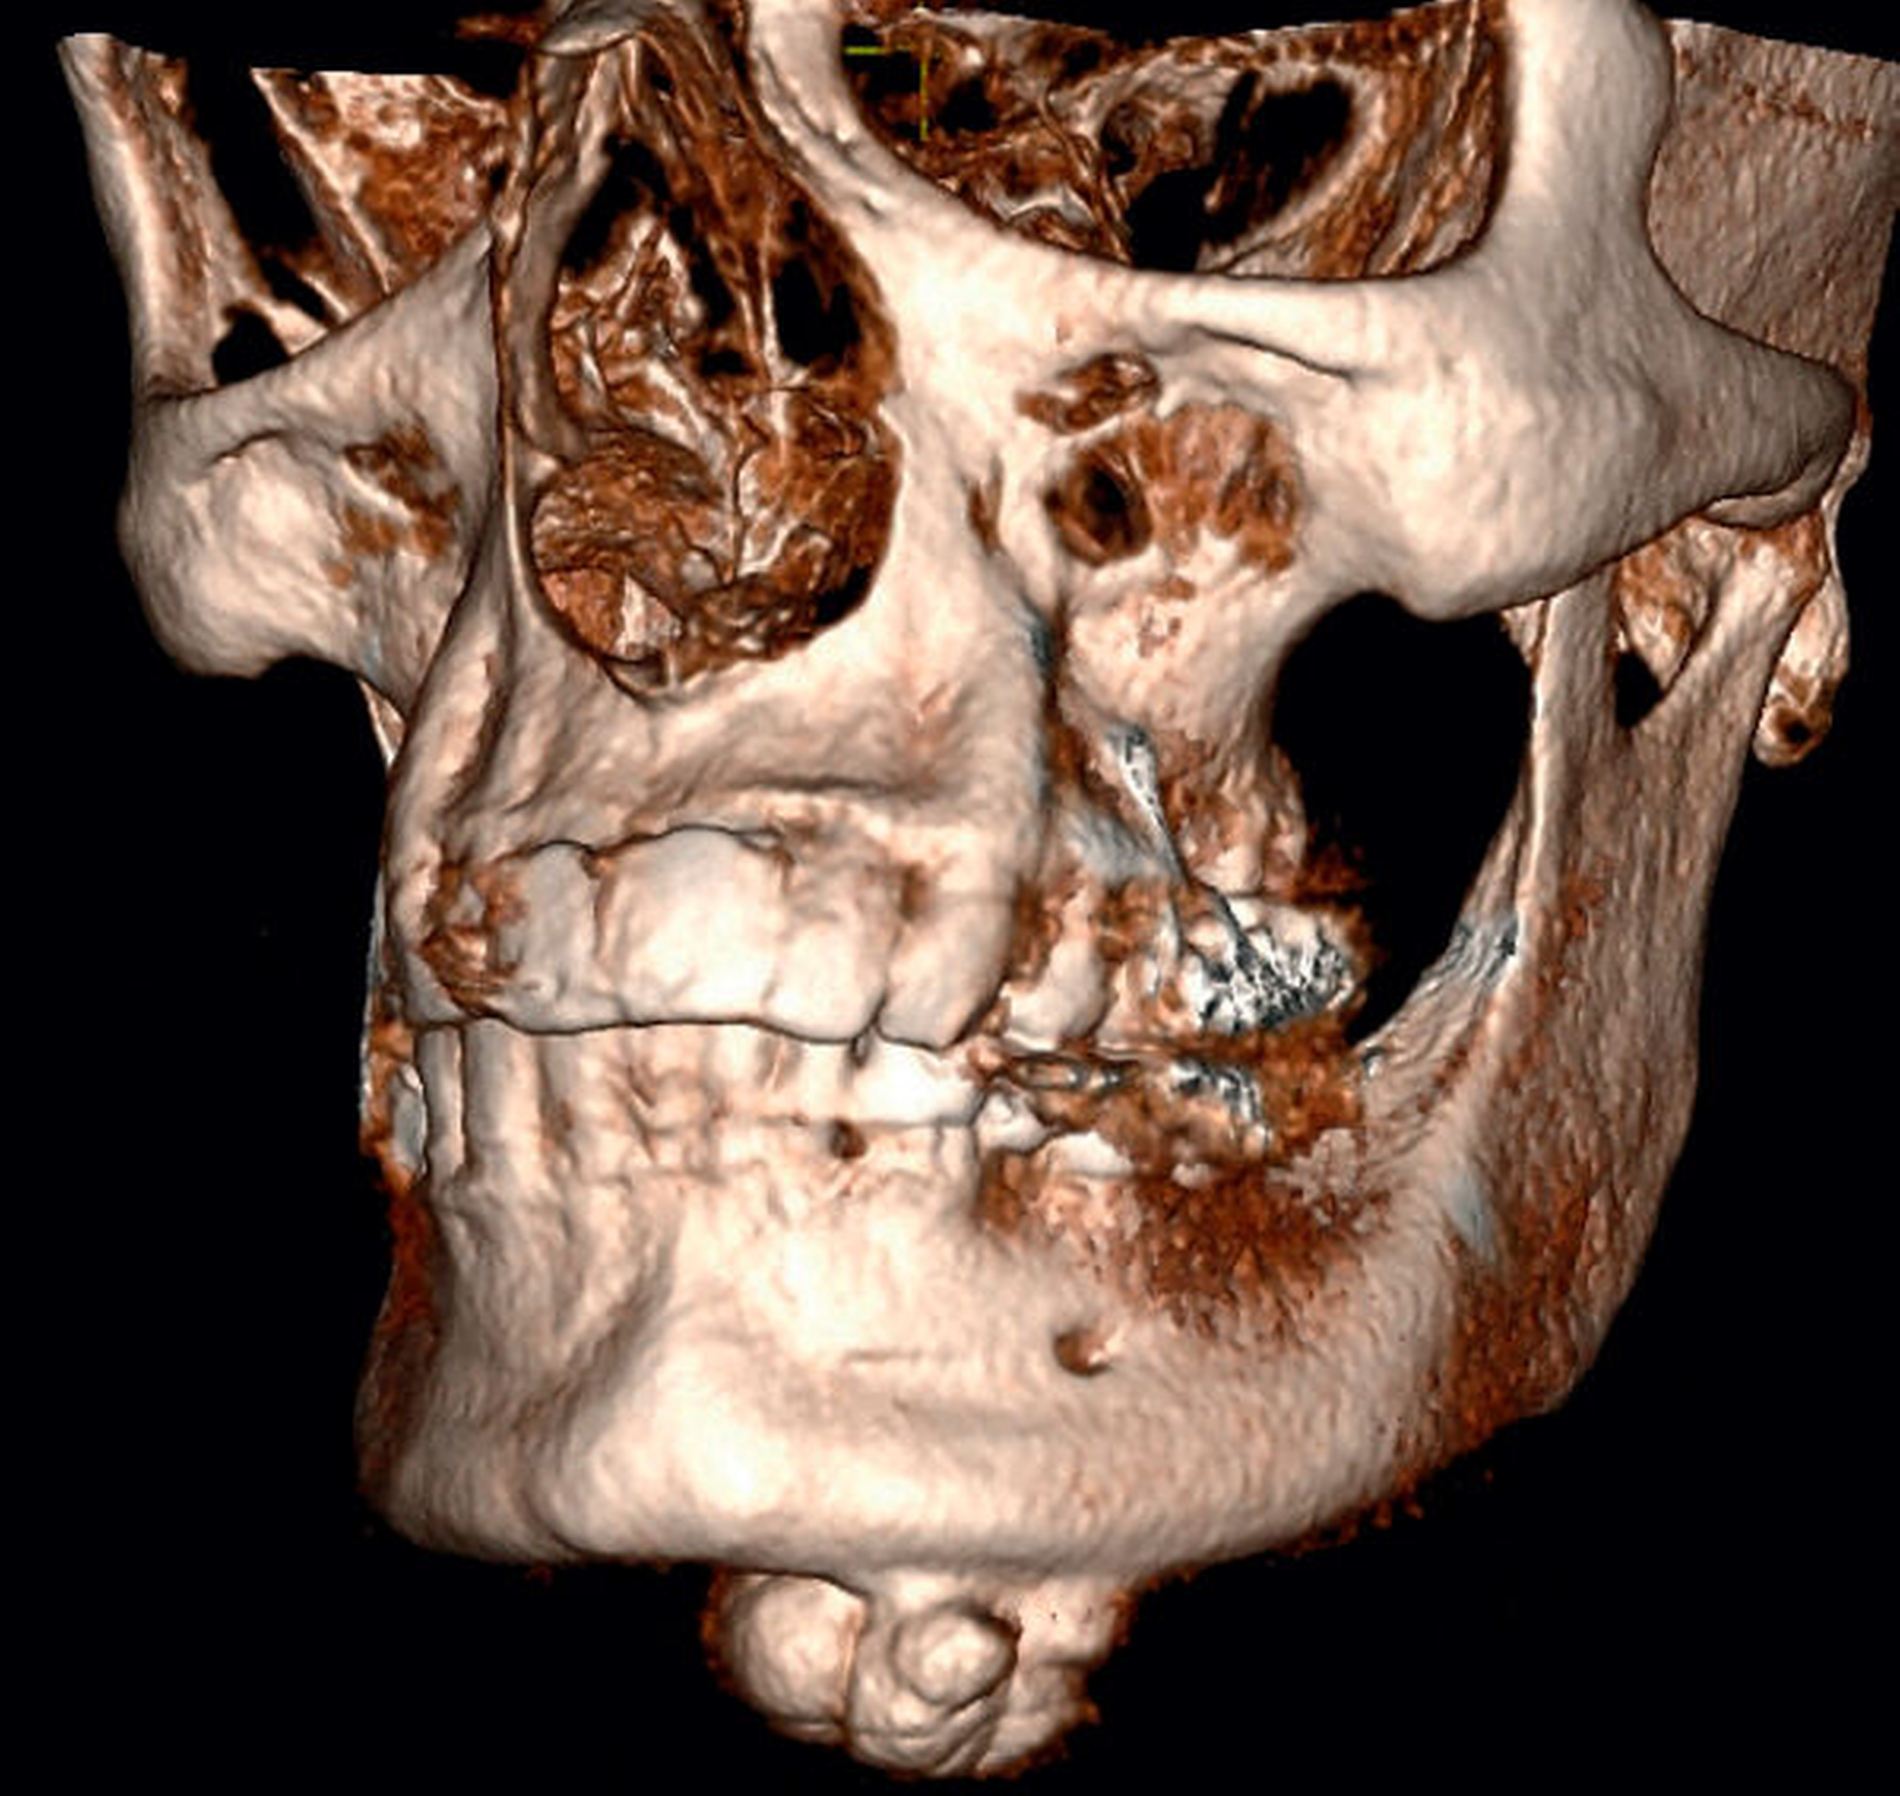

Die zur weiterführenden dreidimensionalen Diagnostik erstellte digitale Volumentomografie (DVT) zeigte eine 1,9 cm x 2,0 cm x 1,4 cm große, nodulär konfigurierte Raumforderung am basalen Unterkieferrand (Abbildung 3). Infolge der klinischen und der radiologischen Untersuchung wurde die Verdachtsdiagnose eines solitären peripheren Osteoms gestellt und der Patient über die geplante Befundexstirpation sowie die dabei bestehenden Operationsrisiken aufgeklärt.

Zwei Wochen später erfolgte die Abtragung der ossär-konfigurierten Raumforderung in Intubationsnarkose von extraoral unter Zuhilfenahme der Piezosurgery® (Abbildung 4).